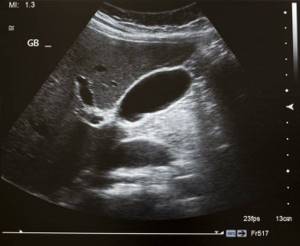

Желчный пузырь играет не последнюю роль в пищеварении человека, помогает рассасывать жиры и стимулирует выработку ферментов. Отказ этого органа, даже частичный

При этом возникает застой желчи. Для полноценного функционирования человеческого организма необходимо вывести разжиженную желчь. Сделать это можно несколькими способами.